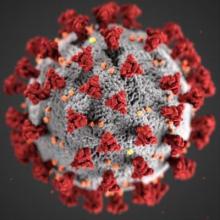

The rapid spread of the coronavirus (SARS-CoV-2) and the disease it causes (COVID-19) impacts all of us in many ways. This disease not only affects us physically, but also mentally and emotionally. For cancer patients, this pandemic adds to already existing stress and may worsen ongoing health… more

Given the rapid rise of COVID-19 cases around the world, scientists and clinicians are looking into the possible effects of common medications on COVID-19 progression and outcomes. Two medications commonly found on cancer patients' medication lists include non-steroidal anti-inflammatory drugs (… more

The coronavirus (SARS-CoV-2) that causes COVID-19 (the disease) is more dangerous to people with other health conditions, including cancer.

Please visit the National Cancer Institute's information page for people with cancer.